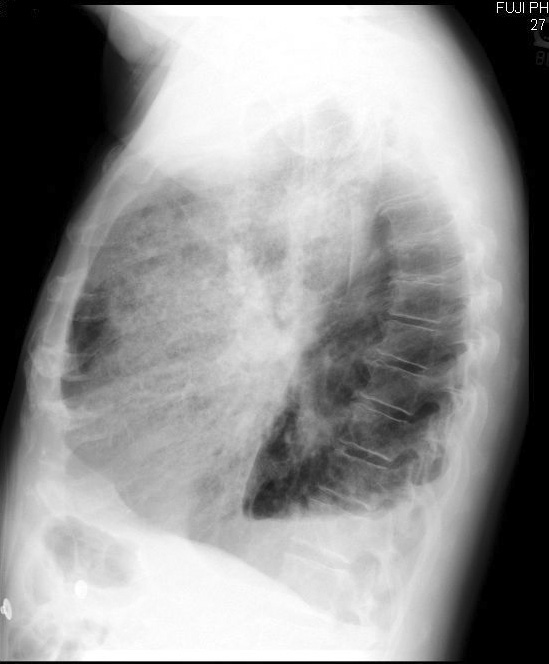

The Left upper lobe opacity represents pulmonary hemorrhage. There is also a

left pleural effusion seen best as a fluid level on the lateral view.

12)

Based on your findings, what lobe is involved in the above image? Left

upper lobe.